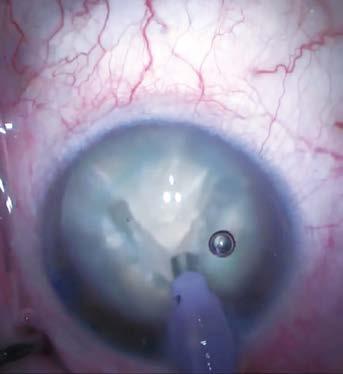

A la exploración, se encuentra agudeza visual de ojo derecho 20/40, ojo izquierdo percepción de luz, con presión intraocular de ambos ojos de 12 mmHg (tonómetro de Goldmann), segmento anterior sin alteraciones de importancia, pseudofaco y fondo de ojo izquierdo con una hemorragia vítrea grado IV. Se solicita ecografía de ojo izquierdo la cual mostró una hemorragia vítrea con desprendimiento de retina sero-hemático con elevación coroidea de 8.77 mm x 3.14 mm, localizada en cuadrante temporal inferior, con una reflectividad interna baja (33%) (Imagen-1).

Imagen 1. Ecografía de ojo izquierdo: